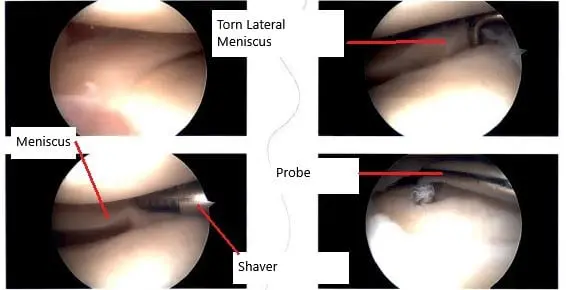

Intraoperative arthroscopic image showing the meniscus tear.

Examination of that medial compartment showed an old healed osteochondral lesion of the lateral surface of the medial femoral compartment which was stable. There was no tear of the medial meniscus. Examination of the intercondylar notch showed intact ACL. Examination of the lateral tibiofemoral compartment showed a tear of the posterior horn of the lateral meniscus. The lateral meniscus posterior horn was debrided using biters and shavers.

Examination of the patellofemoral compartment again shows an osteoarthritic lesion of the medial facet of the patella which was debrided using a shaver. The arthroscope was entered through the medial portal and findings were re-confirmed and final images were saved.